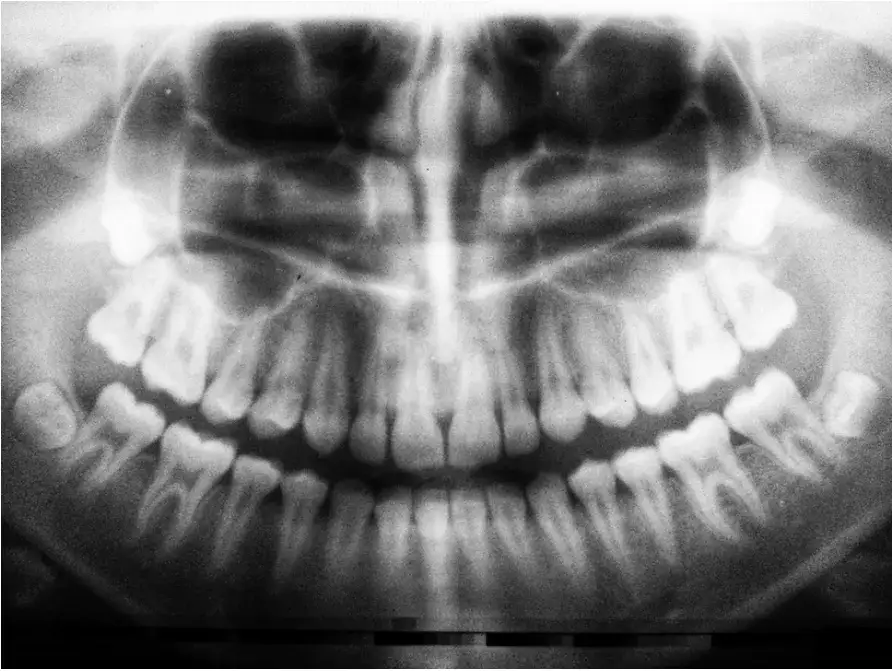

Diagnostyka w takich przypadkach opiera się na dokładnym wywiadzie lekarskim oraz badaniu stomatologicznym. Dentysta może zlecić zdjęcie rentgenowskie, aby ocenić stan korzeni zęba i wykluczyć inne przyczyny bólu. Warto pamiętać, że wczesne rozpoznanie problemu może zapobiec poważniejszym komplikacjom.

Jeśli ból głowy od zęba nie ustępuje pomimo leczenia stomatologicznego, warto rozważyć wykonanie dodatkowych badań. Zdjęcie rentgenowskie zęba to podstawowe narzędzie diagnostyczne, które pozwala ocenić stan korzeni i tkanek otaczających. W niektórych przypadkach konieczne może być również wykonanie tomografii komputerowej, aby wykluczyć inne przyczyny bólu.